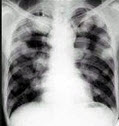

28、单项选择题

男,56岁,痰中带血1月余,X线检查如图,最可能的诊断是()

A.两肺炎症

B.肺转移瘤

C.血行播散型肺结核

D.细支气管肺泡癌

E.矽肺